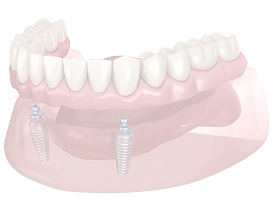

1歯から全顎まで。

オールオン4にも対応

• 1歯欠損のインプラント

• 複数歯欠損への治療計画

• 全顎治療(オールオン4)

※適応の可否は、骨・噛み合わせ・全身状態などから判断します。

全顎治療(オールオン4)

歯がほとんどない・総入れ歯が合わない等のお悩みで、条件が合う場合に選択肢となります。

※適応の可否は、骨・噛み合わせ・全身状態等により判断します。